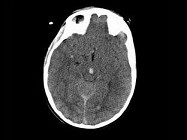

- 单项选择题男,25岁, 头颅外伤,昏迷, 意识丧失,结合CT图像, 最可能的诊断是 ( )

A、结节性硬化病

B、脑剪切伤

C、脑囊虫病

D、脑实质钙化灶

E、脑转移瘤